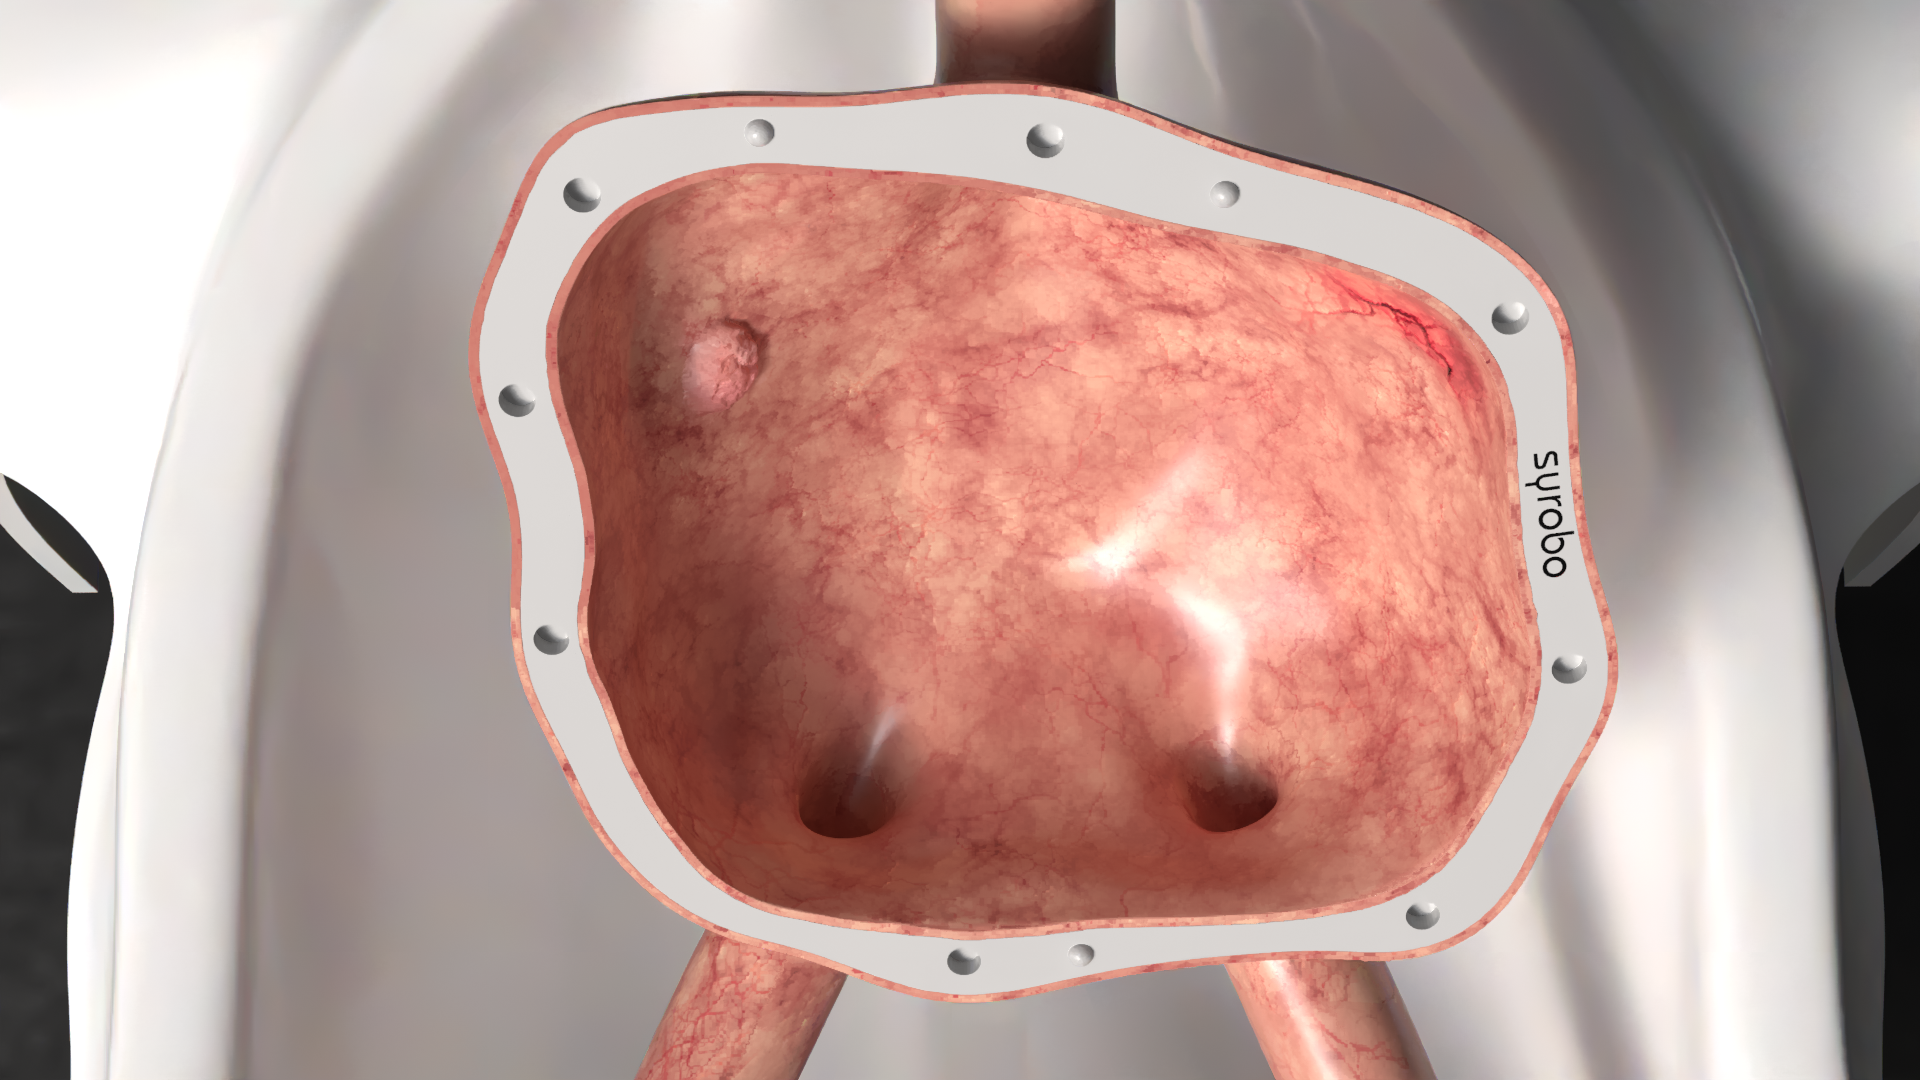

The urinary tract components are removable, and feature covers to facilitate the positioning of removable kidney stones or tumors. The model is supplied with dummy stones and removable magnetized tumors.